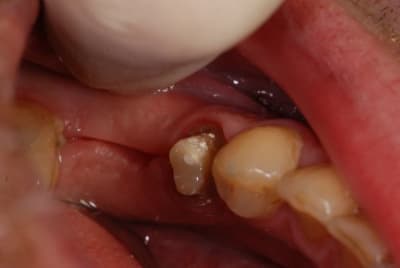

Le mien me sort ça en CCM pour 80 € (12 13). L'autre photo c'est un onlay composite transitoire Adoro sur la 11, 45 €. (Mon capteur photo est sale, je sais)

> L'autre photo c'est un onlay

> composite transitoire Adoro sur la 11, 45 €.

C'est un cas spécial : une ado de 11 ans, chute de vélo avec fracture coronaire de 11 sur les 3 faces (cf photo le jour de la chute). J'ai tenté 2 composites qui n'ont pas tenu. Là le truc a l'air de tenir, même si j'ai de très gros doutes sur la rétention. Après préparation minimale, c'est collé au SmartCem2 (un automordançant, on tente avec ce qu'on a au cab mais le mieux serait un collage au Variolink).

Dans l'avenir j'aimerais que ça tienne jusqu'à la réalisation d'une CCM/CCC sur dent vivante, à la fin de la croissance.